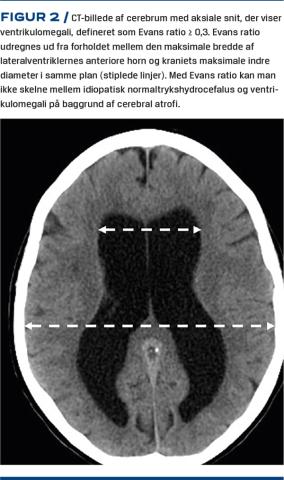

For at man kan stille diagnosen iNPH, skal der være påvist ventrikulomegali med forhøjet Evans ratio (Figur 2). Ventriklerne bliver større med alderen, og ca. 20% af personerne over 70 år har billeddiagnostisk ventrikulomegali[20]. MR-skanning foretrækkes frem for CT ved udredning af iNPH, da karakteristika udover ventrikulomegali kan visualiseres med MR-skanning.